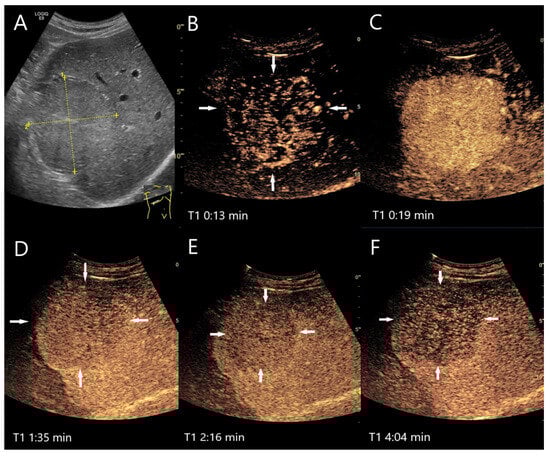

Figure 6.

Inflammatory hepatocellular adenoma. Large mass (between the arrows) in the right lobe of the liver in a male patient (A). In the AP, the lesion shows a diffuse reticular enhancement (B), then a homogeneous hyperenhancement (C). In the PVP at 1:35 min, a shallow washout begins (D), which continues progressively in the LP (E,F). Histology after surgical resection confirmed the HCA.